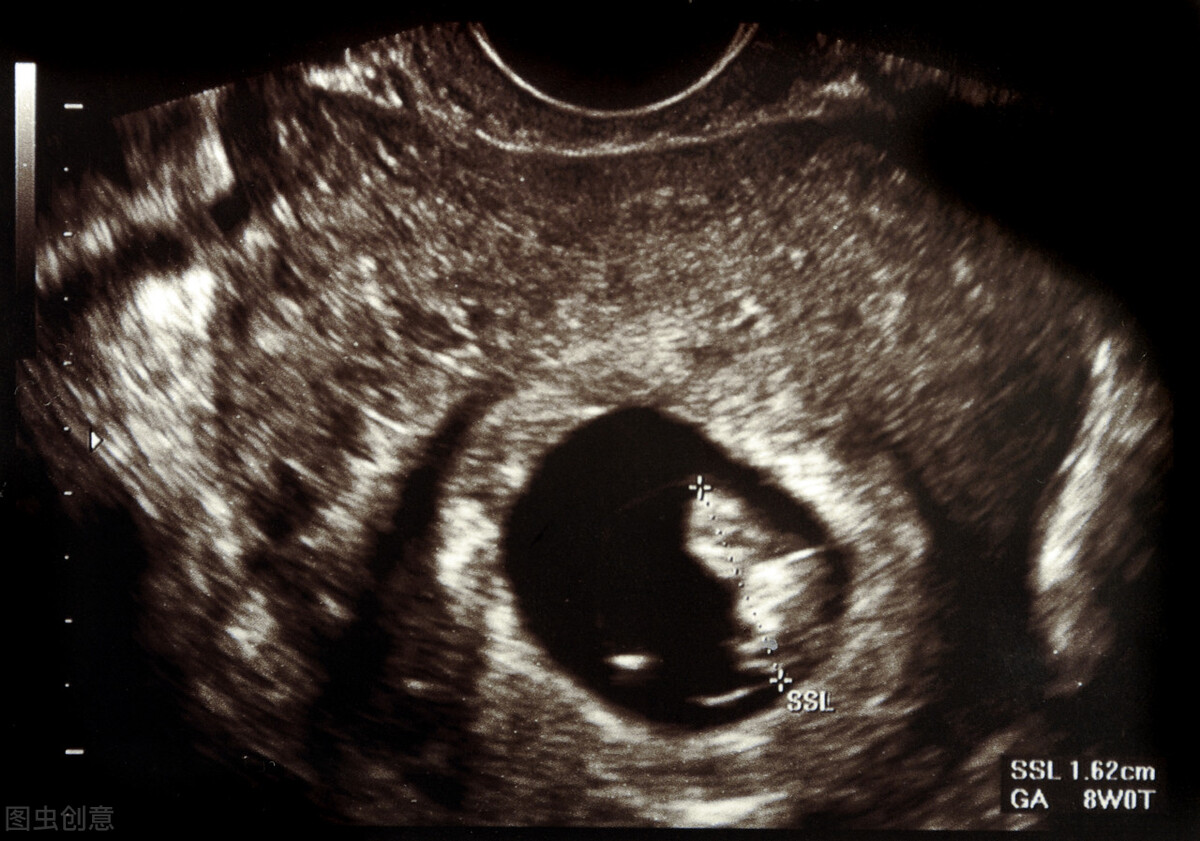

孕8周:宝宝进入发展阶段,尾部慢慢消失,眼睛位于头部的两侧,而不是正前方。宝宝会简单的运动,踢腿、抬手,但妈妈还感受不到。